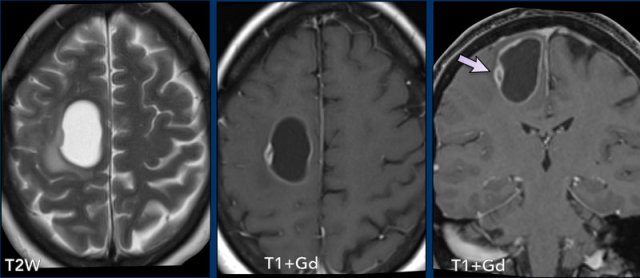

Meningioma

Which findings are typical for the diagnosis meningioma?

Findings:

- The tumor is extra-axial as can be seen on the T2W-image. There is CSF between the tumor and the brain parenchyma, this is called a CSF-cleft

- On T2W image the tumor has a relative low signal intensity

- There is homogeneous enhancement.

- Dural tail (arrowheads)

- Hyperostosis of the skull (asterix).

- The tumor has a flat dural base.

- Most important finding is the CSF between the tumor and the surrounding brain tissue (arrow heads). This finding definitely makes this an extra-axial tumor.

- Low signal on T2W

- Reactive changes in the skull (asterix) There is osseous involvement of the lesion. Not typical but frequently seen in a meningioma